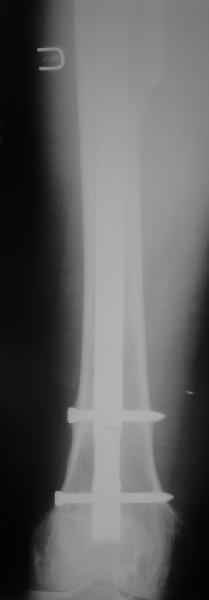

Произведено закрытое удлинение ножки эндопротеза с помощью ретроградного интрамедуллярного стержня. Продолжительность операции 3 часа. Два из них закрытое восстановление длины бедра диистрактором

таз-бедро.

А нельзя ли увидеть и профиль бедра на всем протяжении, т.е. и весь протез, и весь стержень? И фас бы с коленом.

новые снимки